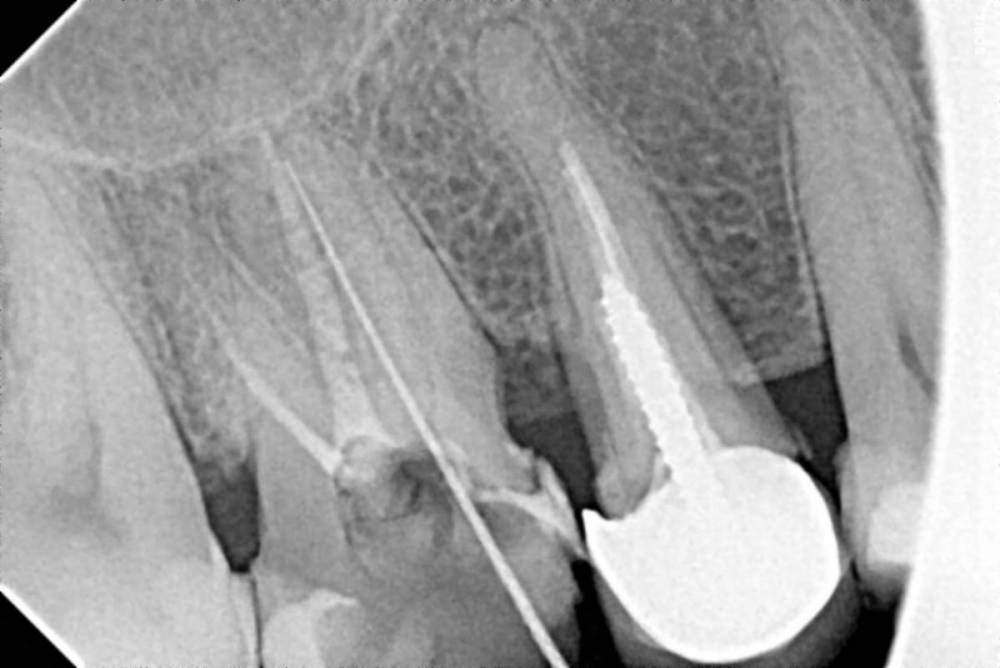

Рабин Опубликовано 2 апреля, 2021 Поделиться Опубликовано 2 апреля, 2021 Уважаемые врачи по снимкам вы видите воспаление или кисту на зубе? Спасибо! Ссылка на комментарий

сирена Опубликовано 3 апреля, 2021 Поделиться Опубликовано 3 апреля, 2021 5 часов назад, Рабин сказал: Снимки не показательны? Иногда на прицельном снимке ничего криминального не видно,а на КТ обнаруживается очаг. Можно маленькую КТ сделать,только в области этого зуба(5Х5 см) 2 Ссылка на комментарий

Рабин Опубликовано 18 мая, 2021 Автор Поделиться Опубликовано 18 мая, 2021 Добрый день! Сделала КТ этого зуба, как вы просили... https://cloud.mail.ru/stock/kkbze24nzBzfEqnUbdPwtsei Видите ли вы воспаление на нём и можно ли его спасти? Интересует также соседний 15 зуб. Спасибо! Ссылка на комментарий

wladdX Опубликовано 18 мая, 2021 Поделиться Опубликовано 18 мая, 2021 (изменено) Зуб 16, на мой взгляд, придётся удалить. Зуб 18 тоже Зуб 15 вроде бы и не вызывает особых восторгов, но и явного неприятия тоже. Изменено 18 мая, 2021 пользователем wladdX 2 Ссылка на комментарий

red_butler Опубликовано 20 мая, 2021 Поделиться Опубликовано 20 мая, 2021 18.05.2021 в 23:24, wladdX сказал: Зуб 16, на мой взгляд, придётся удалить. +1 Ссылка на комментарий

wladdX Опубликовано 29 мая, 2021 Поделиться Опубликовано 29 мая, 2021 18 - там приличных размеров корневая гранулёма, излечить нереально 1 Ссылка на комментарий